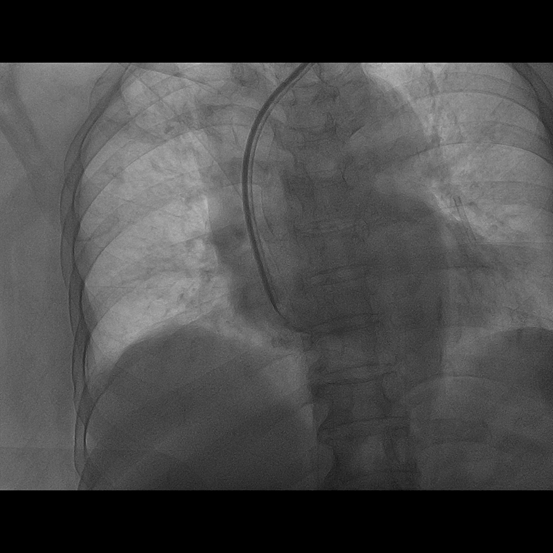

72岁钟阿姨,患尿毒症3年多,长期在我院维持性血液透析治疗,有糖尿病基础疾病,血管条件差,无法行动静脉内瘘手术建立血管通路。钟阿姨曾于2012年底在我院植入右侧颈内静脉半永久透析管,1年后因管路血流不通畅,予以行左侧颈内静脉半永久透析导管术,继续规律血液透析,近期因管路血流量不佳入我院住院治疗。入院后查CTV提示左侧颈内静脉纤细,上腔静脉怀疑血栓,右侧颈内静脉狭窄。由于考虑手术风险高,手术难度较大,肾内科严跃红主任医师邀请广州市第一人民医院放射介入科陈国东副主任医师,联合我院心血管介入科邓天明副主任医师和DSA室医护人员,术前全面评估,术中精细操作,血管造影显示:左侧锁骨下静脉、头臂静脉、上腔静脉上中段狭窄,上腔静脉下段完全闭塞,遂用三个球囊对狭窄闭塞的静脉血管进行逐级扩张成形后,上腔静脉血管复通,DSA引导下辅助半永久透析导管植入,手术成功。

该手术为钟阿姨建立了良好的血管通路,重建了她透析之路的“生命线”,解决了临床棘手的问题,该项技术的成功开展标志着我院血液透析血管通路的建立和介入手术方面取得新的突破。

置入长期透析导管